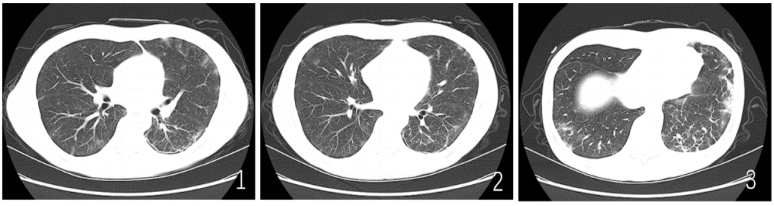

患者2021年8月因“颈部淋巴结肿大”确诊“前T细胞急性淋巴细胞白血病”,行6次化疗(VDCLP方案)。期间患者反复出现脓毒症,病原菌包括阴沟肠杆菌、伊丽莎白菌、大肠埃希菌、白色念珠菌等。此后患者长期服用西他沙星至移植前。2022年4月底患者行骨髓移植(姐姐,异基因半相合)。出院后长期口服环孢素(200 mg bid,逐渐减量至此次入院前早50 mg,晚25 mg)抗排异、泊沙康唑口服混悬液(200 mg tid)预防真菌感染至入院。2022年5月患者出现发热、咳嗽、咳痰等不适,就诊于广州医科大学附属第一医院,诊断“巨细胞病毒肺炎”,予更昔洛韦静脉抗感染半月余,出院后继续服用缬更昔洛韦半月。2022年9月起患者每2周复查血巨细胞病毒核酸、EB病毒核酸均未见明显异常,末次复查时间为2022年10月12日。2022年10月26日复查骨髓穿刺提示完全缓解,胸部CT:双肺炎症,左肺下叶间质性改变,右肺下叶、左肺上叶多发实性结节(图1。患者自觉略有疲乏、稀便每日2~3次,入院前半月已好转。现为进一步诊治就诊于我院。既往史、个人史及家族史均无特殊。

图1  患者2022年10月26日胸部CT:双肺炎症